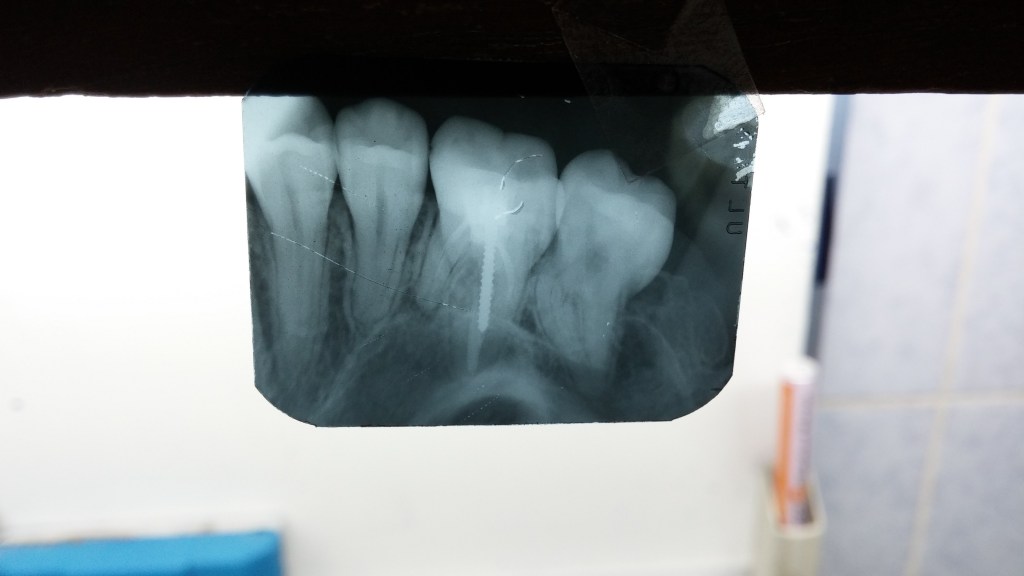

Don’t Remove. (before X-ray) radix-ento พบได้ในคนไทย 12.7% Germination X-ray ช่วยให้เห็นสิ่งที่ซ่อนอยู่ภายใน สังเกต furcation ก็รู้ว่าฟัน Perio Mermaid Premolar ให้สังเกตที่ mouth mirror เห็นถึงความฝ้ามัว เป็น Br พม่าครับ alloy ไม่แข็งมาก X-ray เท่านั้นจึงจะรื้อได้ ผมจะชอบวัดความยาวของฟันบ่อยๆ เทียบกับความยาวในใจที่เดาเอาไว้ RCT incomplete ใครสังเกตเห็นความผิดปกติบ้างครับ? ถึงกับต้องถ่ายทุกมุมเลยซี่นี้ remove ฟัน Crowding เป็น PVC ล้อมด้วยฟัน RCT อย่าลืม X-ray ก่อนถอนนะครับ Share this: Share on X (Opens in new window) X Share on Facebook (Opens in new window) Facebook Like Loading... Uncategorized